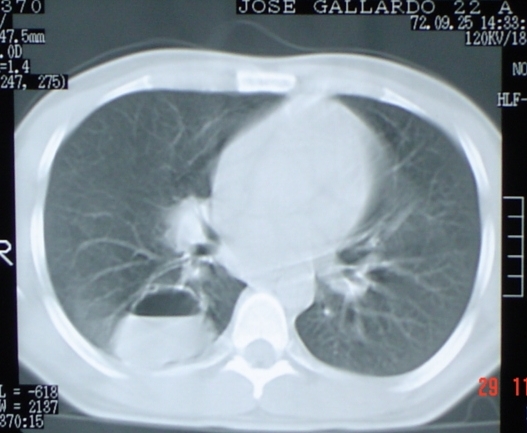

- <div style=fiogf49gjkf0dFig. 3. Se aprecia imagen radioopaca compatible con cavidad neumónica que muestra nuvel líquido interior localizada en base pulmonar derecha. ">

Fig. 3. Se aprecia imagen radioopaca compatible con cavidad neumónica que muestra nuvel líquido interior localizada en base pulmonar derecha.